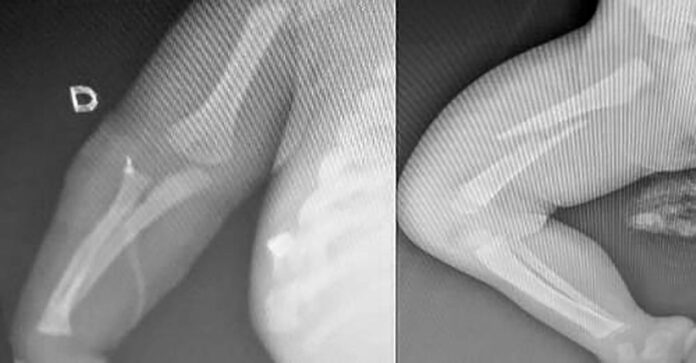

Inicialmente, segundo o boletim de ocorrência, o pai havia relatado que o bebê caiu do colo dele enquanto dormia. Mas, devido à gravidade dos ferimentos, a equipe médica acionou a Guarda. O bebê apresentava diversas fraturas nas pernas, braços e costelas.